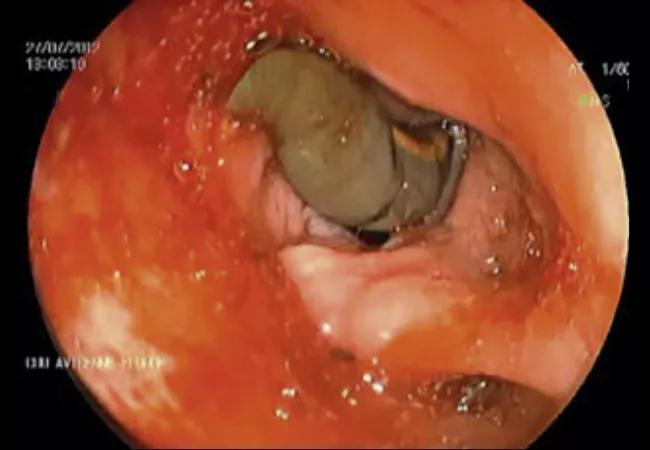

Seventeen cases of leech infestations in the subglottic airway appear in the medical literature. Leeches store blood in sacs called crops in their alimentary canals. These engorge with blood upon feeding. A small leech in the laryngeal inlet may not initially cause symptoms, but acute airway obstruction may occur once the leech is well fed, as in the above image and below video of a live leech in the vocal cords. Leeches can also cause aeromonas infections, which can lead to pneumonia, septicemia, gastroenteritis and meningitis.

Tracheobronchial hirudiniasis often presents with nonspecific respiratory symptoms and can be confirmed with flexible bronchoscopy. Removing a leech in the airway is far more complicated than removing one on the skin. Lidocaine can be used to facilitate the leech’s detachment, but it is important to first grasp the leech so that it does not fall into the distal airways. Recent cases have shown successful extraction from a cryoprobe and cryoadhesion.